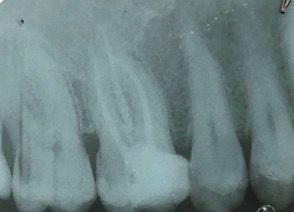

Un trattamento endodontico consiste nel salvare un dente compromesso da carie, traumi o fratture rimuovendone polpa e nervi infetti/infiammati responsabili di dolore, ascessi, cisti e granulomi.

Una corretta terapia canalare con un perfetto sigillo a livello degli apici delle radici è fondamentale. I denti devitalizzati impropriamente possono creare ulteriori problemi che poi andranno a ripercuotersi sulle cure effettuate successivamente come le ricostruzioni e le corone protesiche con conseguente fallimento del piano terapeutico.

Capita spesso di incontrare denti già devitalizzati in maniera impropria che necessitano, seppur asintomatici, di essere ritrattati per evitare che i granulomi infetti visibili radiograficamente si evolvano riassorbendo tutto l’osso sottostante.